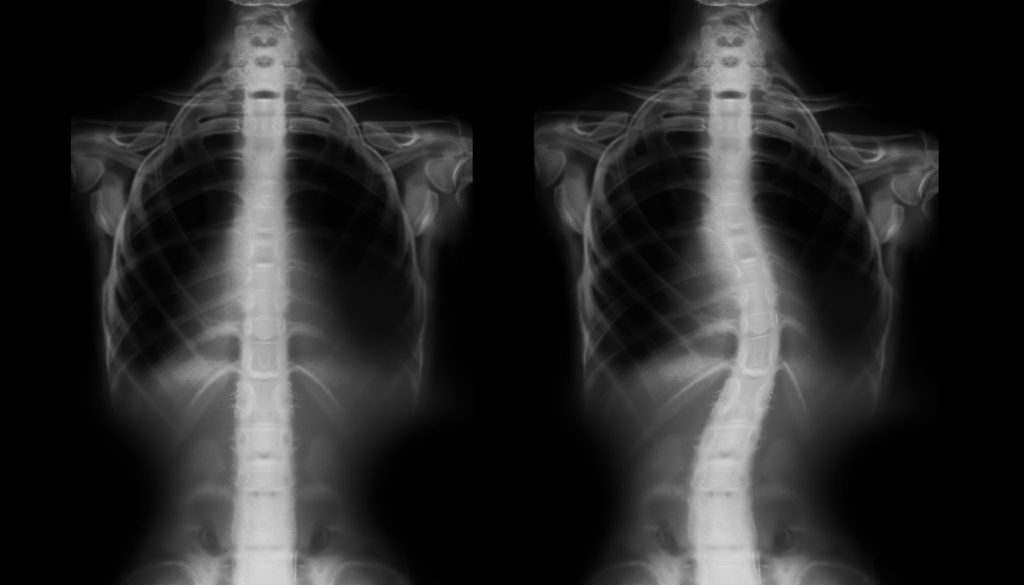

الاعوجاج الخلقي للعمود الفقري هو اضطراب هيكلي ينشأ نتيجة تشوهات خلقية في الفقرات منذ الولادة. يتضمن الاعوجاج الخلقي أنواعًا عديدة مثل “الجنف”، ويسبب تباينًا في انحناء العمود الفقري، مما قد يؤدي إلى مشاكل وظيفية وصحية لاحقة.

– **التصوير بالأشعة**: مثل الأشعة السينية، لإعطاء صورة واضحة عن شكل العمود الفقري.